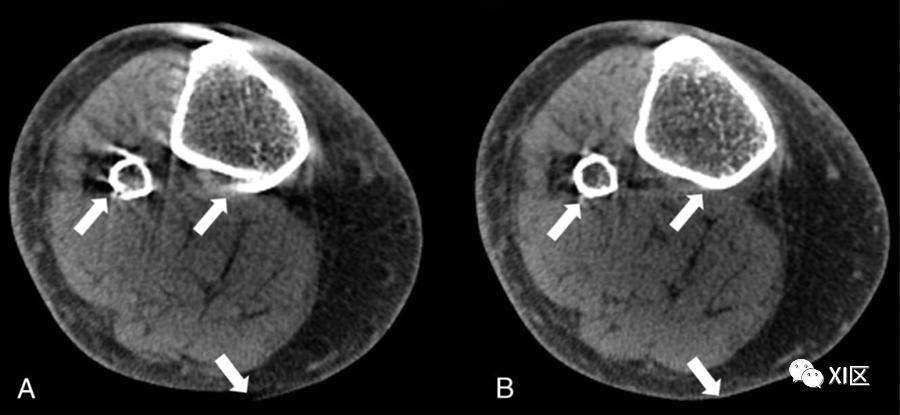

在自动聚焦方法中,通过执行数值优化以估计运动轨迹来实现补偿,该运动轨迹最小化运动引起的图像域失真的某些度量;在肌肉骨骼CBCT中,图像梯度的方差被用作度量。在涉及运动污染的肢体CBCT扫描的专家观察者研究中,自动聚焦校正体积显示出改进的诊断质量(图2)。

图2. WB-CBCT中的自动聚焦运动补偿。A、带有特征伪影图案(条纹和双轮廓)的运动污染扫描(箭头)。B、自动聚焦补偿可显著减少伪影(箭头)。足部和踝关节成像